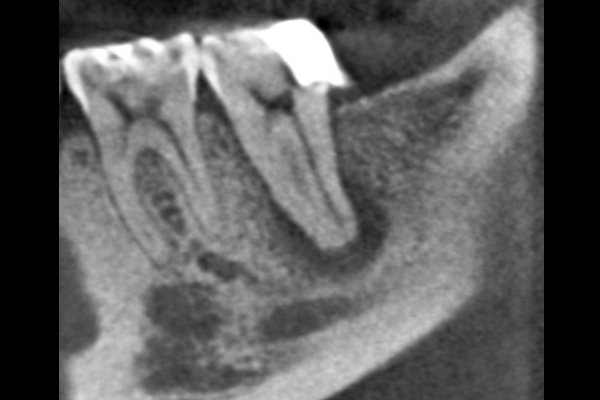

60代男性の大臼歯(奥歯)の症例

- 主訴

- 「時々歯茎が腫れる」とのことでご来院されました。数週間前から症状があり、他の医院では「抜歯の可能性がある」と言われ、不安に感じていらっしゃいました。

- 期間

- 治療期間2ヶ月、治療回数3回、レントゲン写真で治癒を確認できるまでの期間6ヶ月

- 治療内容

- 1.古い被せ物の除去と虫歯の徹底除去 まず、古い銀歯を外し、内部に広がっていた虫歯を丁寧に取り除きました。

2.マイクロスコープ下での根管治療 唾液などによる細菌の侵入を防ぐ「ラバーダム」を装着し、マイクロスコープ(歯科用顕微鏡)で根管内を数十倍に拡大しながら治療を進めました。複雑な形状の根管の内部まで、汚染された組織を徹底的に洗浄・消毒します。

3.根管充填(こんかんじゅうてん) 根管内が完全にクリーンになったことを確認し、再感染を防ぐために専用の薬剤で隙間なく密閉しました。

4.土台と被せ物の作製 歯の強度を補うための土台を立て、最終的なセラミックの被せ物を作製し、装着しました。

- 治療に伴うリスク

- 少しでも汚染物質が残ると再発のリスクが高まります。